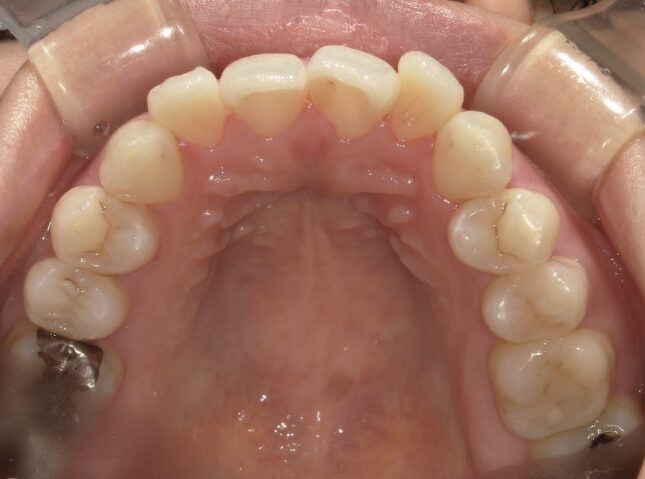

治療前

前歯が全く当たっていないを主訴に当院を受診され、開咬・上顎前突・下顎叢生を認めました。

上顎左右4番抜歯を行いIPRを使用してマウスピース型矯正装置(インビザライン)を使用し、改善を行いました。

抜歯部位上顎左右4番